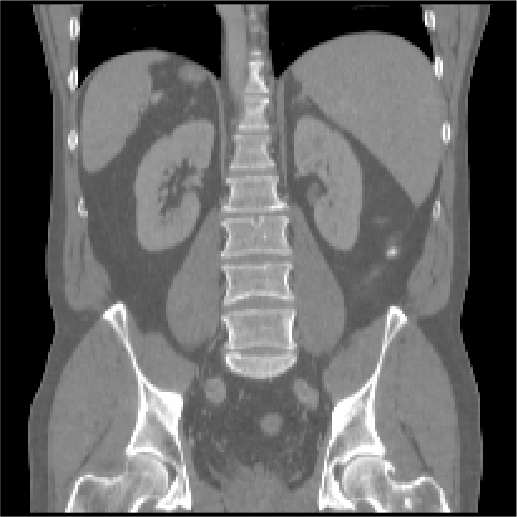

Abdomen MR-CT OASIS Lung CT

Fixed Moving Fixed Moving Fixed Moving

[Uncaptioned image] [Uncaptioned image] [Uncaptioned image] [Uncaptioned image] [Uncaptioned image] [Uncaptioned image]

Modalities MR T1w / CT MR T1w / MR T1w CT / CT

Intra-/Inter-patient Intra-patient Inter-patient Intra-patient

Resolution 192×160×192192160192192{\times}160{\times}192 160×192×224160192224160{\times}192{\times}224 192×192×208192192208192{\times}192{\times}208

Voxel size 2×2×2 mm222timesabsentmillimeter2{\times}2{\times}2$\text{\,}\mathrm{mm}$ 1×1×1 mm111timesabsentmillimeter1{\times}1{\times}1$\text{\,}\mathrm{mm}$ 1.75×1.25×1.75 mm1.751.251.75timesabsentmillimeter1.75{\times}1.25{\times}1.75$\text{\,}\mathrm{mm}$

Cases (Train/Test) 8/8 416/39 20/10

Preprocessing canonical affine pre-align affine pre-align

crop/pad/resample crop/pad/resample

Annotations (Train/Test) 4/9 anatomical labels 35/35 anatomical labels –/100 landmarks/case

Additional data 90 unpaired MR/CT scans lung masks

ROI masks

Metrics DSC/DSC9/HD95 DSC/DSC30/HD95 TRE/TRE30

SDlogJ/RT SDlogJ/RT SDlogJ/RT

Challenges \mathbin{\vbox{\hbox{\scalebox{2.5}{$\bullet$}}}}\mathbin{\vbox{\hbox{\scalebox{2.5}{$\bullet$}}}}\mathbin{\vbox{\hbox{\scalebox{2.5}{$\bullet$}}}}\mathbin{\vbox{\hbox{\scalebox{2.5}{$\bullet$}}}}\mathbin{\vbox{\hbox{\scalebox{2.5}{$\bullet$}}}}\mathbin{\vbox{\hbox{\scalebox{2.5}{$\bullet$}}}}\mathbin{\vbox{\hbox{\scalebox{2.5}{$\bullet$}}}} \mathbin{\vbox{\hbox{\scalebox{2.5}{$\bullet$}}}}\mathbin{\vbox{\hbox{\scalebox{2.5}{$\bullet$}}}} \mathbin{\vbox{\hbox{\scalebox{2.5}{$\bullet$}}}}\mathbin{\vbox{\hbox{\scalebox{2.5}{$\bullet$}}}}\mathbin{\vbox{\hbox{\scalebox{2.5}{$\bullet$}}}}\mathbin{\vbox{\hbox{\scalebox{2.5}{$\bullet$}}}}\mathbin{\vbox{\hbox{\scalebox{2.5}{$\bullet$}}}}\mathbin{\vbox{\hbox{\scalebox{2.5}{$\bullet$}}}}

TABLE I: Overview of all six Learn2Reg tasks addressing the imminent challenges of medical image registration: multi-modal scans \mathbin{\vbox{\hbox{\scalebox{2.0}{$\bullet$}}}} (tasks with at least two different image modalities), few/noisy annotations \mathbin{\vbox{\hbox{\scalebox{2.0}{$\bullet$}}}} (less than five annotated anatomical structures for training cases), partial visibility \mathbin{\vbox{\hbox{\scalebox{2.0}{$\bullet$}}}} (restricted or cropped field of view for at least one image of a registration pair), small datasets \mathbin{\vbox{\hbox{\scalebox{2.0}{$\bullet$}}}} (less than 30 training cases), large deformations \mathbin{\vbox{\hbox{\scalebox{2.0}{$\bullet$}}}} (tasks with initial displacements of at least 10 cm10timesabsentcentimeter10$\text{\,}\mathrm{cm}$), small structures \mathbin{\vbox{\hbox{\scalebox{2.0}{$\bullet$}}}} (tasks containing cases with target structures comprising less than 100 voxels), unsupervised registration \mathbin{\vbox{\hbox{\scalebox{2.0}{$\bullet$}}}} (no annotations for training cases) and missing correspondences \mathbin{\vbox{\hbox{\scalebox{2.0}{$\bullet$}}}} (e.g. due to removed organs, different field of views etc.)

.

Abdomen MR-CT

The data was compiled from public studies of the cancer imaging archive (TCIA) [23] that contained paired scans of both MR and CT from the same patients. In particular, 16 MR and CT scans from the following studies, TCGA-KIRC [24], TCGA-KIRP [25], and TCGA-LIHC [26], are included in Learn2Reg - that cover routine diagnostic scans and follow-up imaging for kidney surgery. The data has been resampled to an isotropic resolution of 2mm, and cropped and padded to achieve voxel dimensions of 192x160x192. We have also manually traced 3D segmentation masks for the liver, spleen, left and right kidney. All scans were pre-aligned using a groupwise affine registration based on the deeds-linear algorithm [27]. Additional unpaired and segmented training data from two further challenges - BCV-CT [12] and CHAOS-MR [28, 29] - were provided for pre-training.